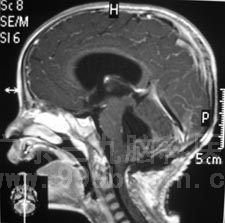

2010年12月1日,小昌在全麻下接受了“右侧脑室腹腔分流术+脑干、四脑室内占位切除术”。术程顺利,术后小昌恢复良好,没有出现抽搐、恶心呕吐等症状,四肢活动良好。术后的病理报告显示:髓母细胞瘤WHO IV级。http://www.999brain.com

术前 术后